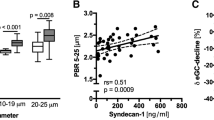

Each of the 8 nurses performed 4 to 7 sets of measurements in 40 additional patients to determine PBR and RBC filling values and evaluate the inter-observer reproducibility during routine care. Mean [± SD] duration of the bedside procedure (without calculations performed by the software) was 6 ± 3 min and the overall quality of the measurements performed by the nurses was evaluated as excellent with a median score of 4 (3–4) by the physician (A.R.). There were no differences between the nurses’ and the physician’s values for PBR: 2.43 (2.23–2.62) vs. 2.39 (2.24–2.59) μm, p = 0.74, and RBC filling percentage: 60.7 (53.99–64.45) vs. 60.18 (54.84–66.03) %, p = 0.45, respectively (Fig. 2a and Additional File 2: Figure S2). In fact, the subsequent measurements taken by the nurses and the physician were strongly correlated (rs = 0.63, p < 0.0001). The ICC analysis showed excellent reproducibility between the nurses’ and physician’s PBR of 0.75 (95% CI: 0.52–0.87) and RBC filling percentage of 0.81 (95% CI: 0.64–0.90). Comparisons made using the Bland-Altman method showed a good agreement between the nurses’ and physician’s PBR assessment (Fig. 2b). The mean difference between the two PBRs (bias) was 0.007 ± 0.25 μm. There was no statistically significant heterogeneity between the performance of the different nurses (p = 0.12). The nurses’ PBR assessment had a 90% sensitivity (95% CI: 60–99%) and 90% specificity (95% CI: 80–93%) to identify a severely impaired glycocalyx (PBR ≥ 2.59, n = 10/40 patients – 3 patients in the ER group and 7 in the ICU group).

Inter-observer reproducibility of Perfused Boundary Region (PBR) measured by the nurses and physician. Eight trained nurses and a physician obtained paired sets of measurements (random order) in a total of 40 patients (n = 25 in the ER and n = 15 in the ICU) to determine the inter-observer reproducibility. a Boxplots showing PBR values (in μm) obtained by the nurses and the physician. The Wilcoxon signed-rank test was used to compare the paired PBR values. b Bland-Altman plot showing the limits of agreement (bias ±1.96 SD) between paired values for the nurses’ and physician’s perfused boundary region (PBR) measurements. (ER: Emergency Department, ICU: Intensive Care Unit, PBR: perfused boundary region, RBC: red blood cell